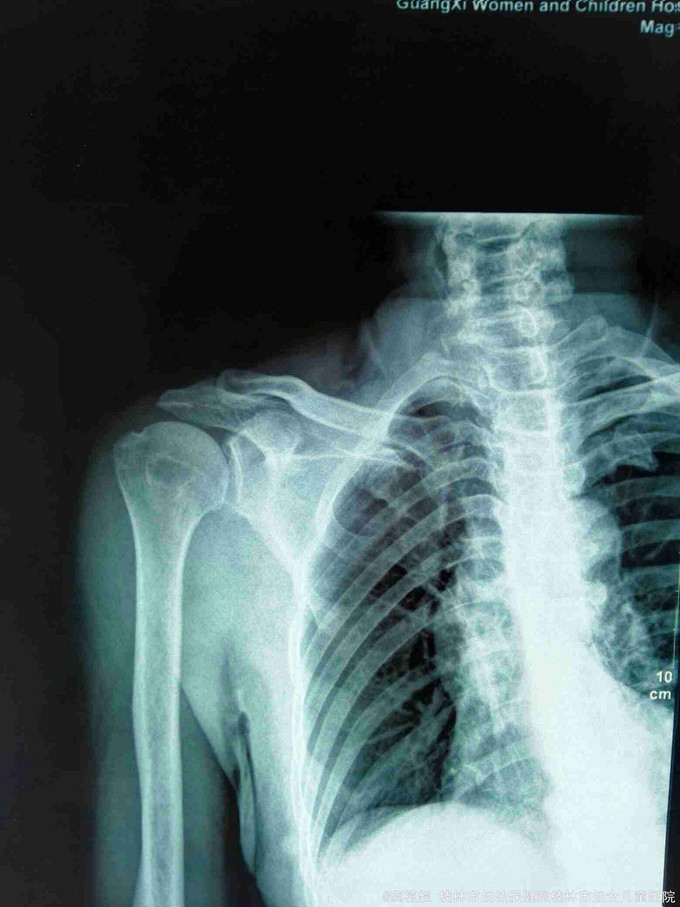

主诉:右肩外伤后疼痛、活动受限27天。 现病史:患者于2015年9月12日不慎跌倒右肩部先着地,右肩部剧烈疼痛、活动受限。肢体无麻木。在家自行外敷草药,症状无缓解。于2015年9月15日到我院门诊行X线检查提示右侧肩关节脱位。门诊予徒手复位术,疼痛明显缓解。术后复查X线示右肩关节复位良好,但患者诉右肩关节仍不能活动,同时伴有右小指麻木,第3、4指伸直受限。近3日上症加重遂来我院,行右上肢肌电图检查提示‘右侧臂丛神经损伤’,予收住院进一步诊治。饮食、睡眠、二便正常。